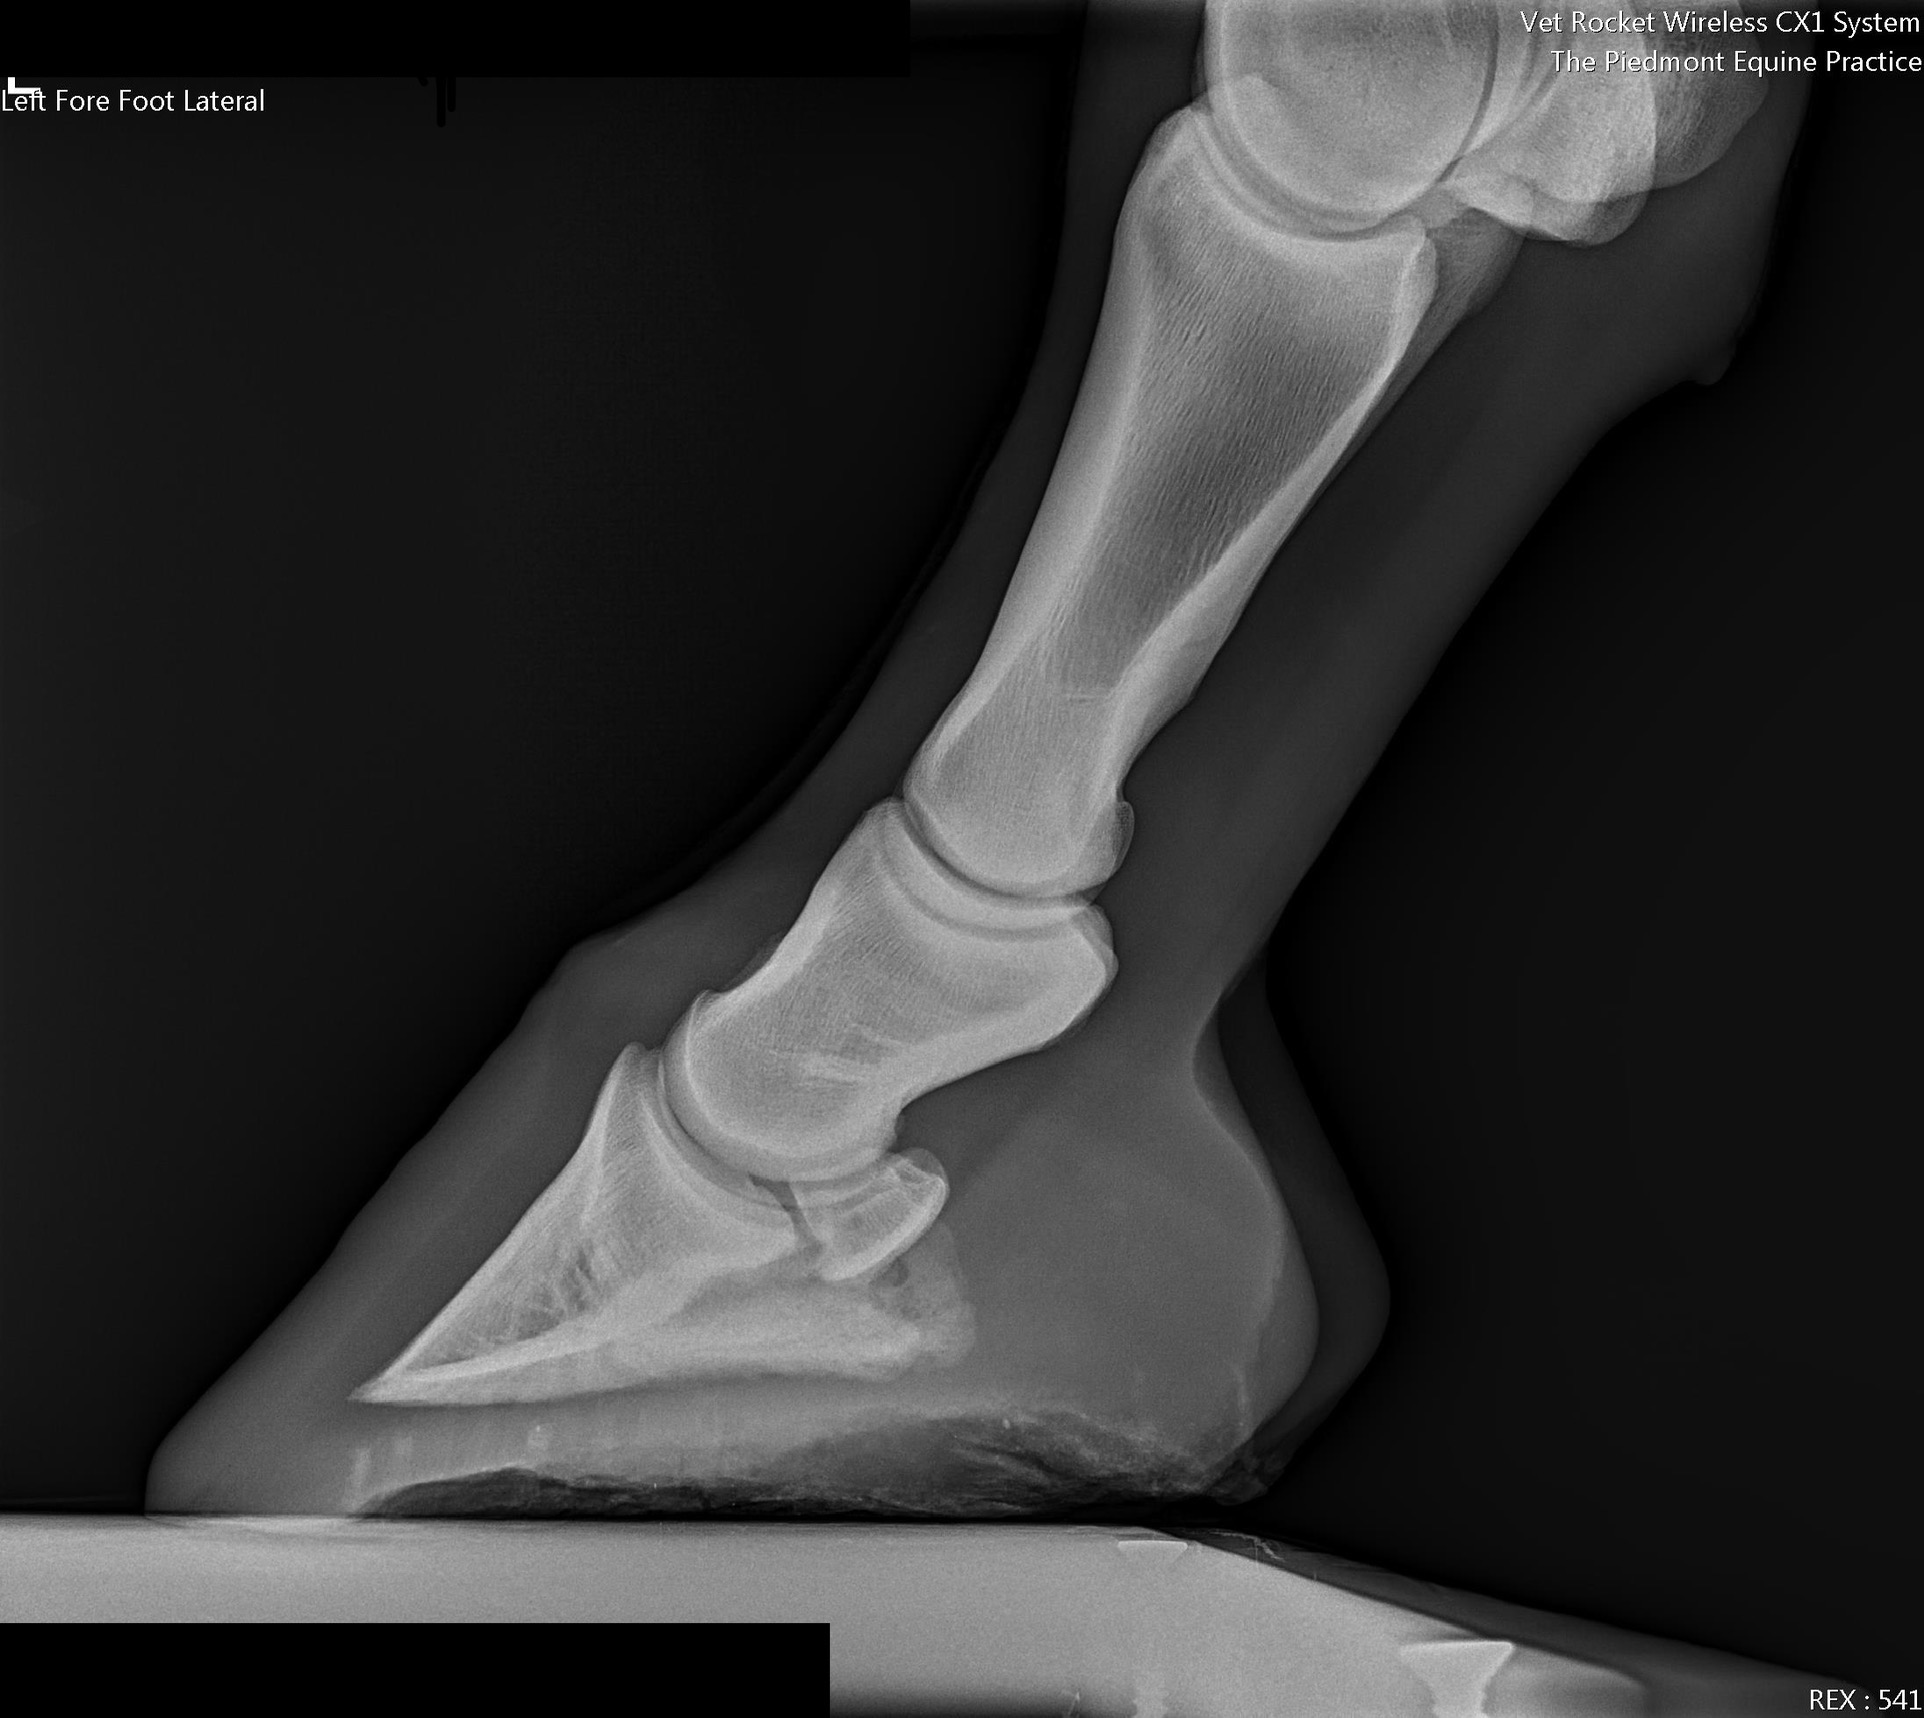

Lameness and Pre-purchase Exams can be performed on the farm in most situations. Portable digital radiography and ultrasonography can be scheduled in advance for a farm call when needed.